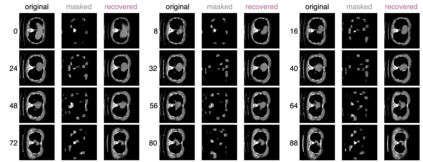

Recently, masked image modeling (MIM) has gained considerable attention due to its capacity to learn from vast amounts of unlabeled data and has been demonstrated to be effective on a wide variety of vision tasks involving natural images. Meanwhile, the potential of self-supervised learning in modeling 3D medical images is anticipated to be immense due to the high quantities of unlabeled images, and the expense and difficulty of quality labels. However, MIM's applicability to medical images remains uncertain. In this paper, we demonstrate that masked image modeling approaches can also advance 3D medical images analysis in addition to natural images. We study how masked image modeling strategies leverage performance from the viewpoints of 3D medical image segmentation as a representative downstream task: i) when compared to naive contrastive learning, masked image modeling approaches accelerate the convergence of supervised training even faster (1.40$\times$) and ultimately produce a higher dice score; ii) predicting raw voxel values with a high masking ratio and a relatively smaller patch size is non-trivial self-supervised pretext-task for medical images modeling; iii) a lightweight decoder or projection head design for reconstruction is powerful for masked image modeling on 3D medical images which speeds up training and reduce cost; iv) finally, we also investigate the effectiveness of MIM methods under different practical scenarios where different image resolutions and labeled data ratios are applied.